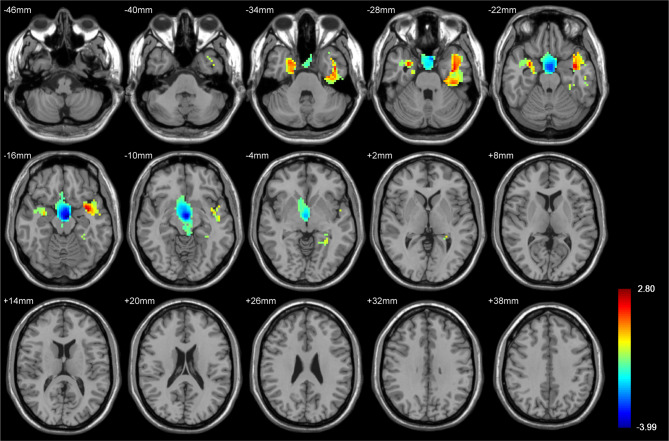

Results: Voxel-based morphometric analysis showed significant positive t-scores within bilateral temporal cortex and negative t-scores in basal ganglia between epilepsy and non-epilepsy groups. Eight radiomics features were identified as significant predictors of epilepsy in LGG, encompassing characteristics of 2 locations, 2 shapes, 1 image gray scale intensity, and 3 textures. The most important predictor was temporal lobe involvement, followed by high dependence high grey level emphasis, elongation, area density, information correlation 1, midbrain and intensity range. The Linear Support Vector Machine (SVM) model yielded the best prediction performance, when implemented with a combination of radiomics features and tumor location features, as evidenced by the following metrics: precision (0.955), recall (0.913), specificity (0.960), accuracy (0.938), F-1 score (0.933), and area under curve (AUC) (0.950).